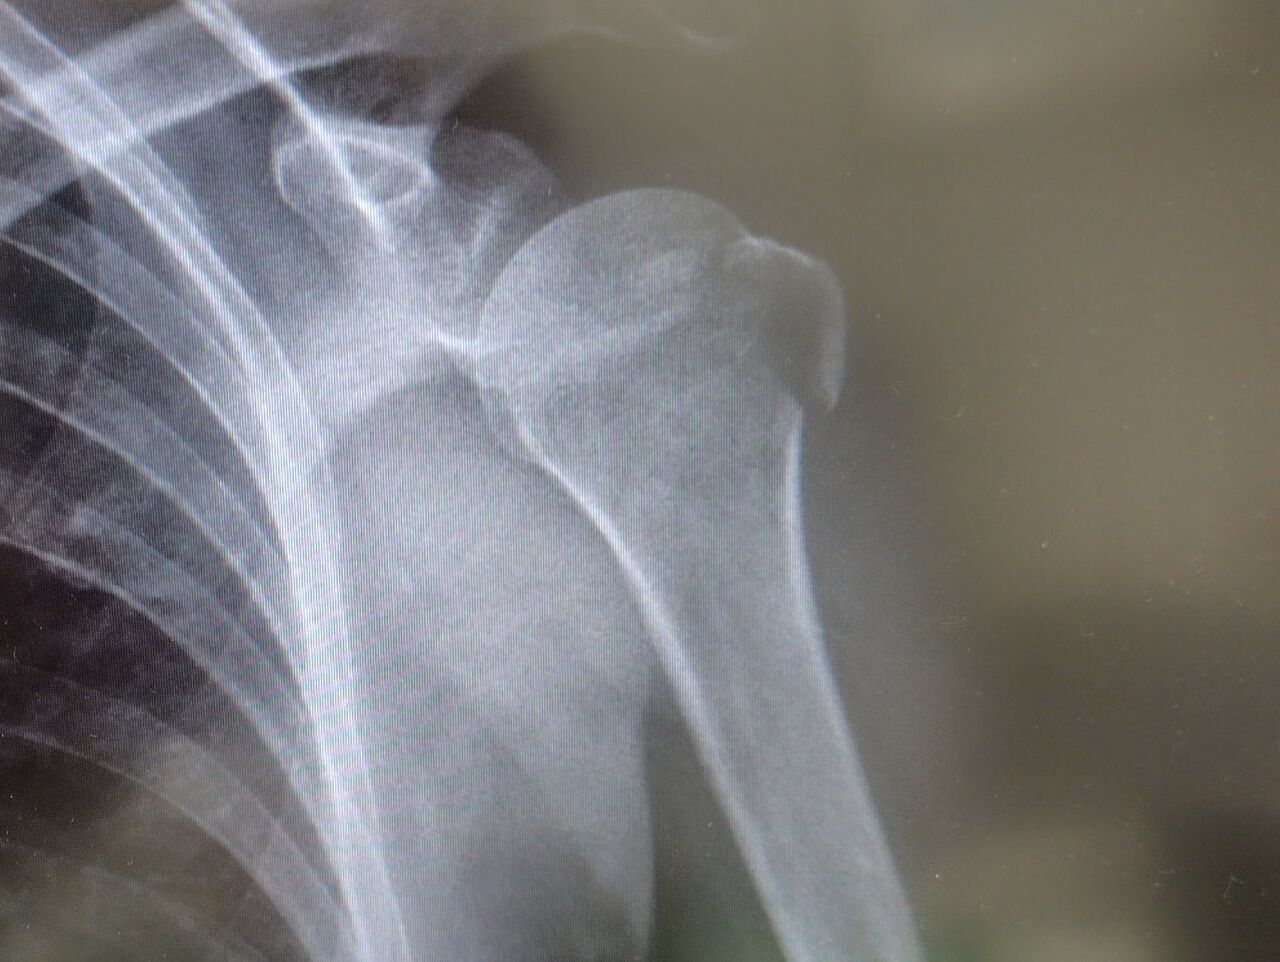

夫婦揃って肩を負傷中💧ブログの題名と違う話しが続きますがご勘弁を🙏

骨折した翌日に病院へ行った時の事。